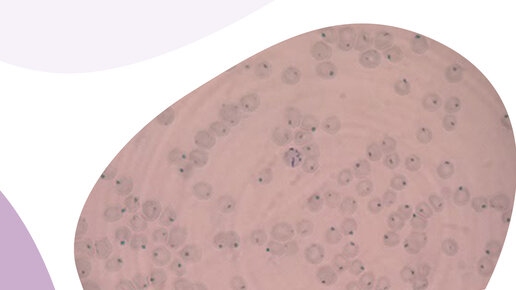

Клетки включения в эритроцитах: тельца Гейнца-Эрлиха и Хауэлла-Жолли

Тельца Гейнца-Эрлиха и Хауэлла-Жолли в мазке крови Собака При исследовании мазков крови животных разных видов можно обнаружить типичные и нетипичные клетки включения или тельца в эритроцитах. Тельца Хауэлла-Жолли Мелкие круглые фиолетово-красные включения. Причины повышения количества телец Хауэлла-Жоли: При обнаружении данных телец в большом количестве или у видов животных, для которых данные включения не характерны, ставится обязательная отметка о находке в гематологической карте. Тельца Гейнца...